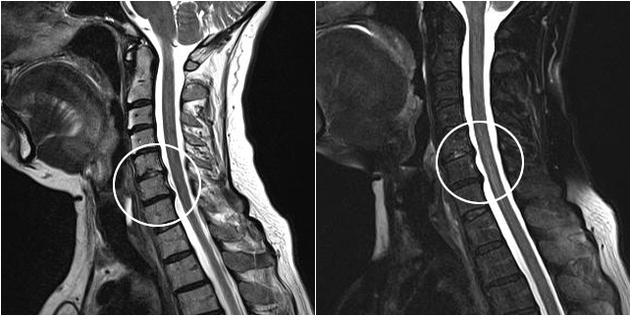

Modern diagnostic methods include MRI and CT, which allow for the most accurate examination of cartilage and bone tissue destruction processes.In addition, this technique is convenient for diagnosing hernia and other soft tissue defects near the source of the disease.